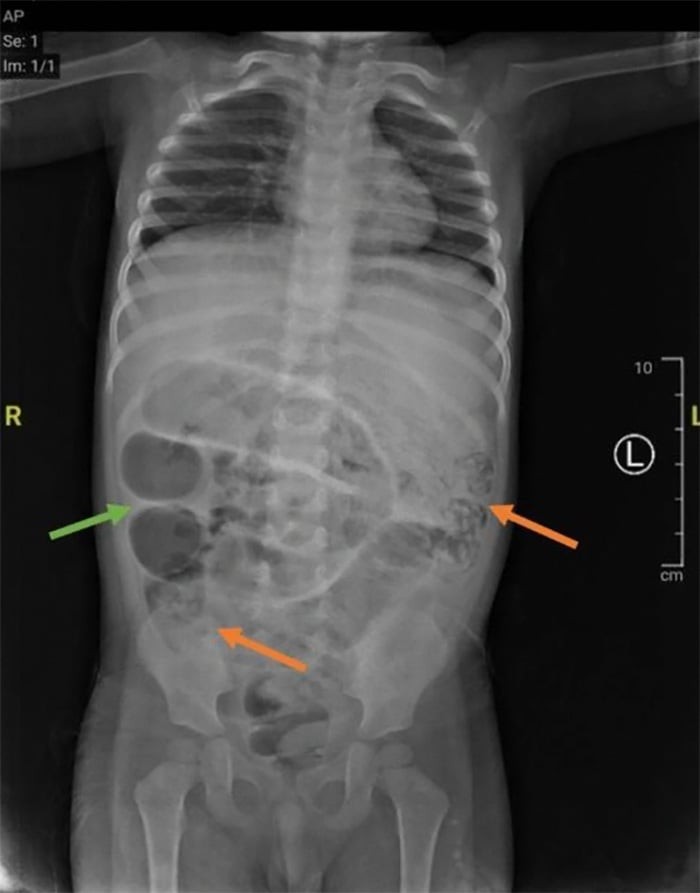

จากนั้น จึงทำการตรวจเช็กร่างกายเด็กอย่างละเอียดอีกครั้ง ผลออกมาว่า มีภาวะโลหิตจางและเม็ดเลือดขาวสูง ผลเอกซเรย์ช่องท้อง แสดงให้เห็นการอุดตันในลำไส้ ทีมแพทย์จึงต้องใเร่งทำการผ่าตัดรักษาอาการในทันที